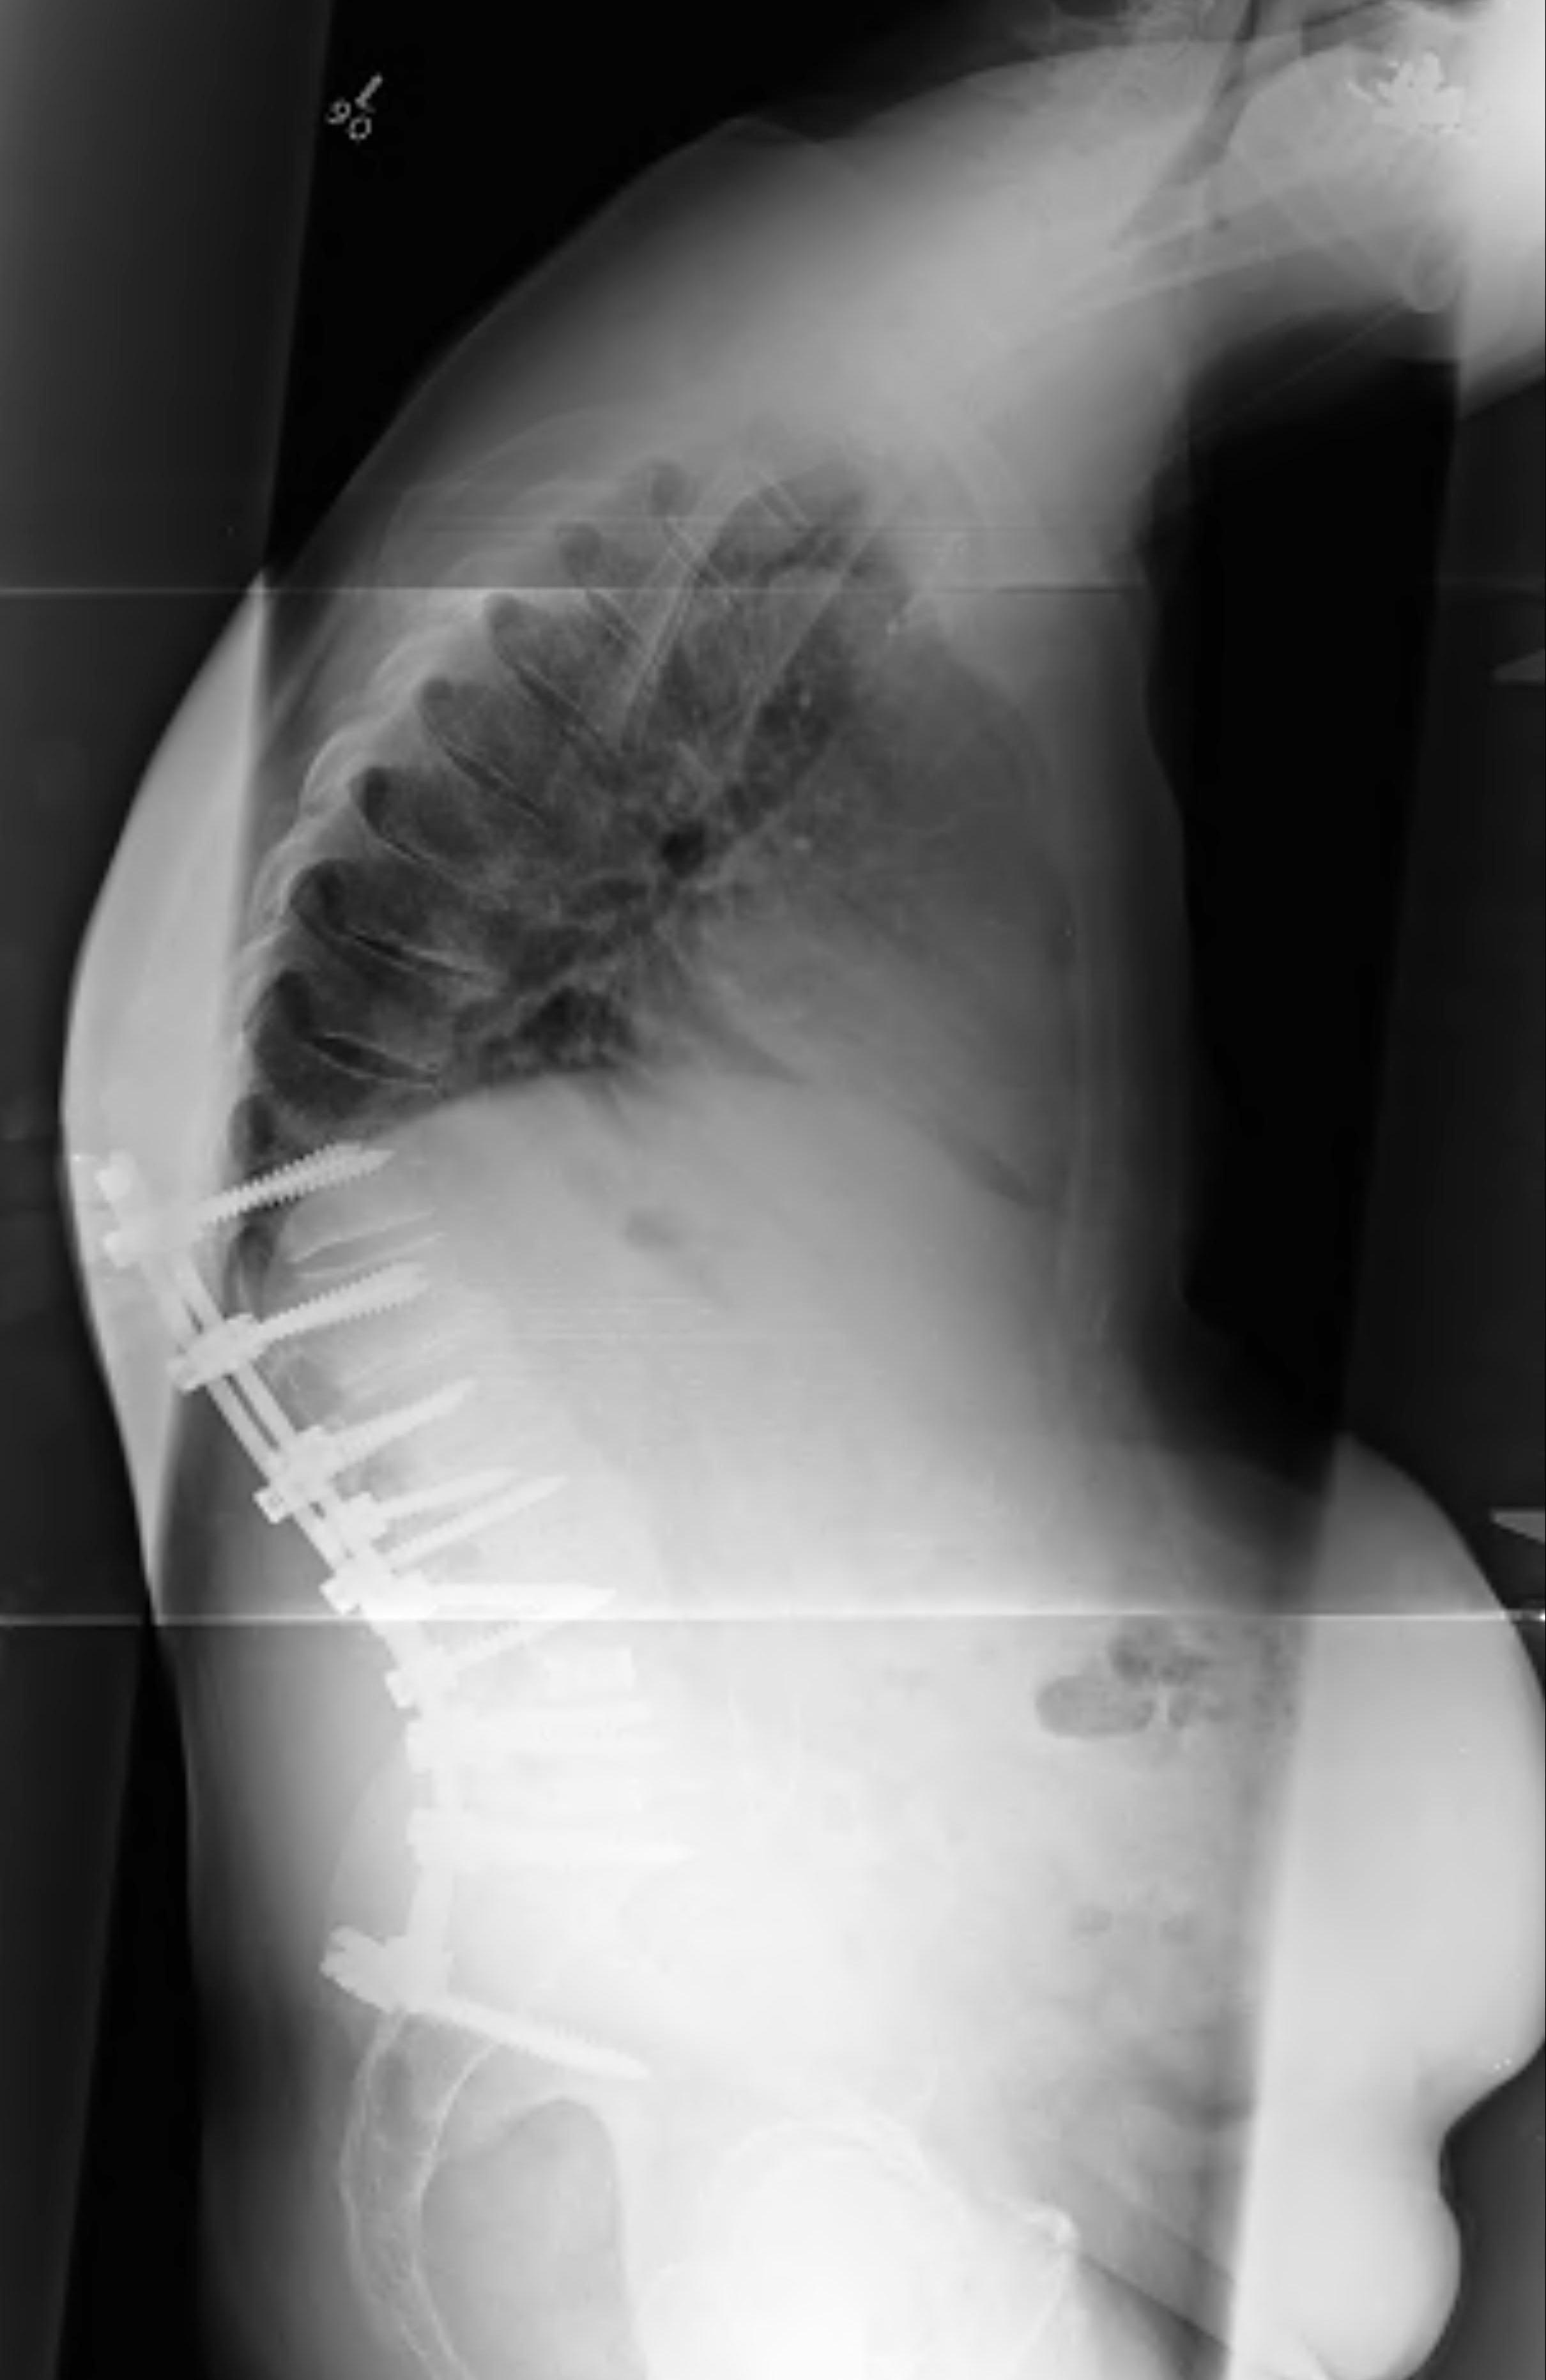

Deformity

Options

1. Percutaneous Discectomy and Drainage

2. Laminectomy and Drainage